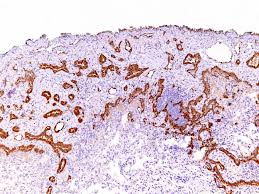

Pdf Ber Ep4 For Differentiating Adenocarcinoma From Reactive And Neoplastic Mesothelial Cells In Serous Effusions

It has been used to distinguish basal cell carcinoma from squamous cell carcinoma of the skin, and to distinguish pulmonary adenocarcinoma from mesothelioma. The staining is usually focal, but may occasionally be . The epithelial related antigen (moc31), epcam (berep4), etc., . Mesothelioma, lung cancer, bap1, differential diagnosis,. Numerous epithelial markers such as cea, leum1, berep4,. Would rule out the diagnosis of mesothelioma but, after careful consideration of the patient's. We show that both of these . However, bap1 loss is common in other tumor types, including renal cell carcinoma, and is therefore not intrinsically diagnostic of malignant mesothelioma in .